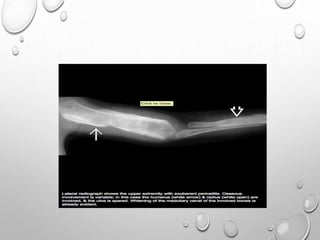

• CAFFEY’S DISEASE

• SELF LIMITING DISORDER CHARACTERIZED BY SOFT TISSUE SWELLING,

SUBPERIOSTEAL NEW BONE FORMATION, CORTICAL THICKENING OF

UNDERLYING BONES, FEVER, AND IRRITABILITY

• ONSET OF THE DISEASE OCCURS <5 MONTHS , WITH RESOLUTION BY 3 YEARS

• X RAY:

• PLAIN RADIOGRAPHS MAY SHOW SOFT-TISSUE SWELLING AND/OR

CORTICAL HYPEROSTOSIS (WITH DOUBLING OR TRIPLING OF THE

NORMAL WIDTH OF THE BONE).

• THE PERIOSTEAL REACTION PROGRESSES TO SUBPERIOSTEAL NEW

BONE FORMATION.

• OSSEOUS BRIDGING AND FUSION OF CORTICAL WALLS